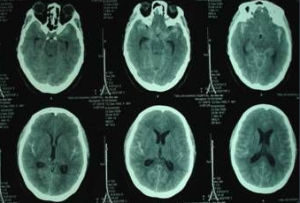

大腦圖片自1988年以來院、所榮獲科研獎勵43項,其中國家獎1項、部級獎24項、市級獎18項,共發表論文2506篇,國際交流論